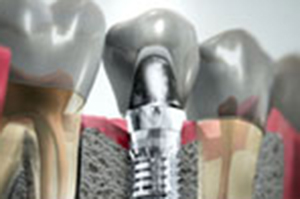

植牙主要是以鈦合金製成的人工植體,來取代原本的牙根,必須透過專業醫師的技術及經驗,精準的將植體植入無牙區域的骨頭內。

植牙補骨的目的,在於能夠讓植牙擁有厚實的牙床、健康穩固的地基,才能幫助人工植牙使用的更長久,承受更大的咀嚼力量。